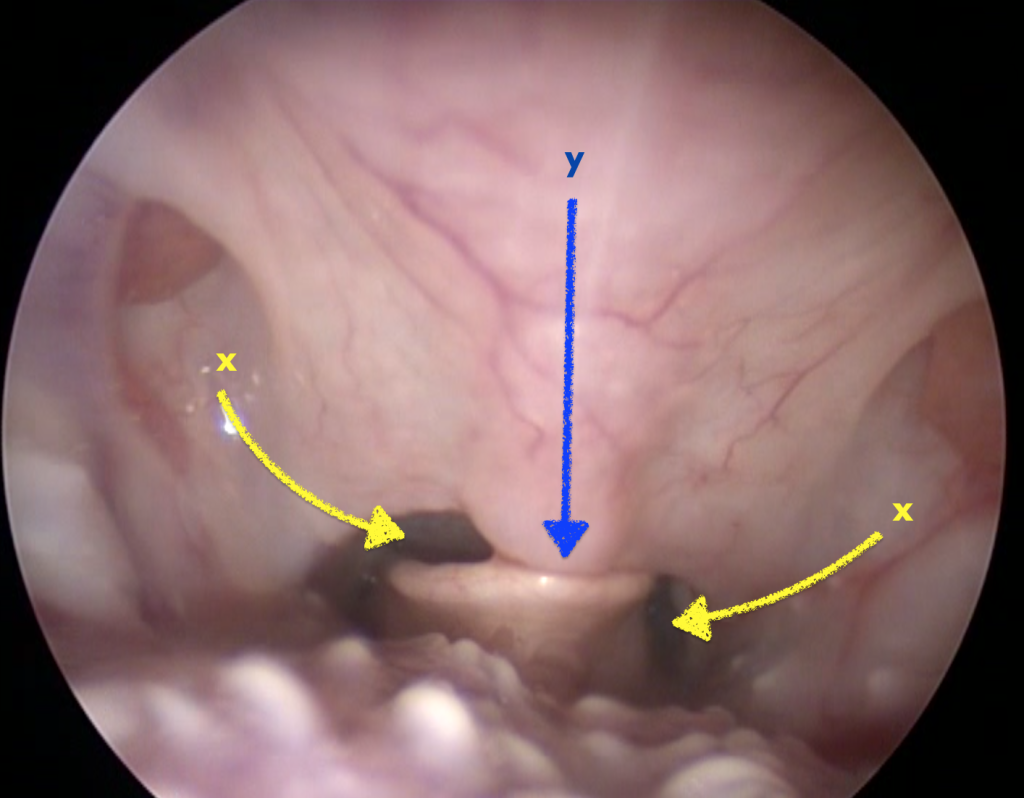

Техника проведения ларингоскопии

Пациент располагается на груди, используется максимально поверхностная седация, голова располагается параллельно туловищу (рис. 2). Позиционирование пациента – очень важный аспект в проведении ларингоскопии. При поднятой голове или широко раскрытой пасти мягкое нёбо смещается каудально, что приводит к некорректной интерпретации результатов исследования.Проводится осмотр гортани и определяется соотношение надгортанника и мягкого нёба. Для корректной оценки необходимо совместить надгортанник с мягким нёбом посредством надавливания пальцем на вентральную часть шеи в проекции корня языка. Пасть при этом должна быть максимально закрыта (рис. 3).

В случае подозрения на наличие ДНФК в процессе проведения ларингоскопии можно наблюдать дорсальное смещение мягкого нёба на вдохе и вентральное – на выдохе.

Всем пациентам была проведена резекция мягкого нёба. Критерием длины резекции нёба являлось соприкосновение только верхушки надгортанника с мягким нёбом в положении пациента с закрытой пастью и опущенной головой во время проведения ларингоскопии. Важно провести резекцию нёба таким образом, чтобы сохранялось сообщение ротовой полости с полостью носоглотки билатерально от надгортанника (рис. 6).Всем пациентам также была проведена ринопластика методом латеральной клиновидной резекции6 (рис. 7).